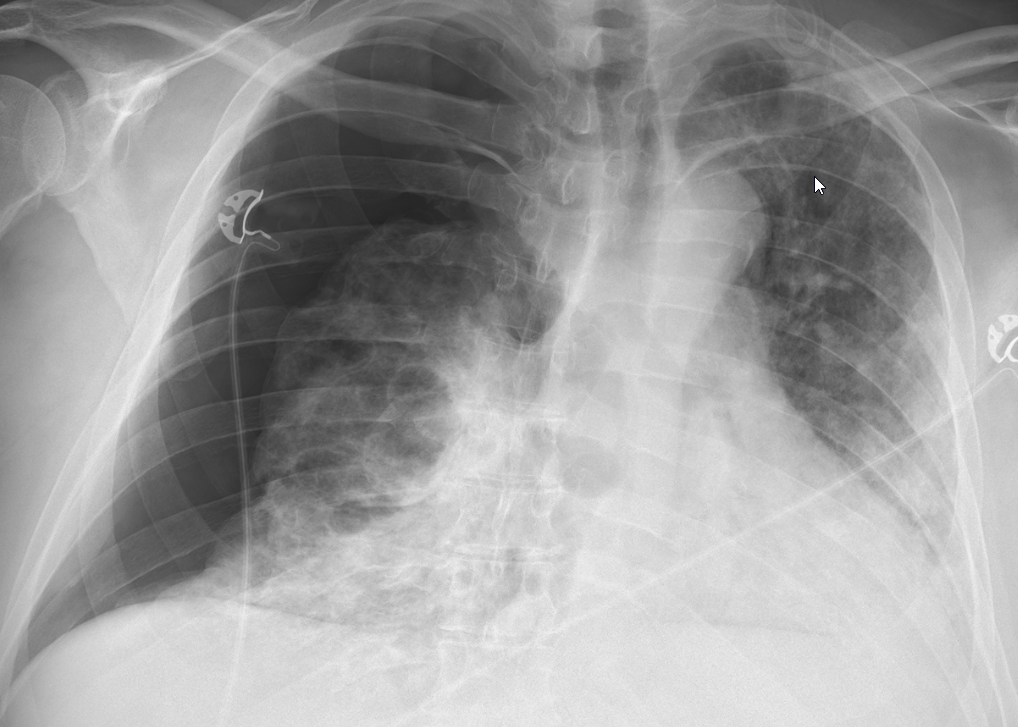

Quick chart review: middle-aged pt admitted w ARDS > 1 month ago. Already w tracheostomy + PEG. Still unable to be weaned on trach mask, despite being on "moderate" fio2 of 40-50%. On iv sedation; drowsy, hemodynamically stable. Not febrile or acidotic. No "weird" labs. CXR: